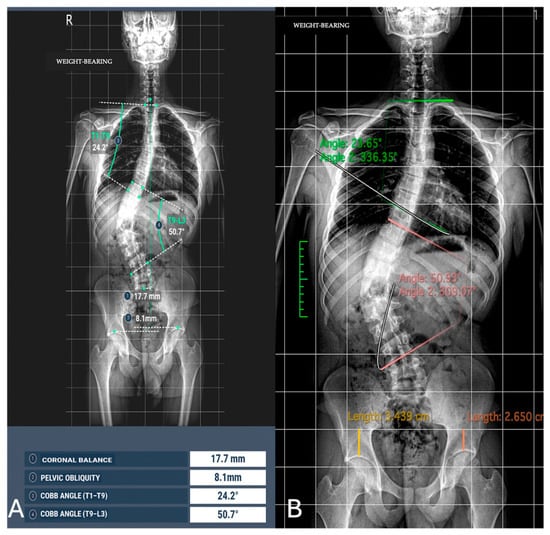

From an initial population of 67 patients, a total of 56 were included in the study (21 males, 35 females). The participants had a mean age of 33.65 ± 24.51 years (range 7–74 years). Among the included subjects, 23 were underage patients. Images with severe artifacts (n = 9) and patients who refused to provide informed consent (n = 2) were excluded from the analysis. Pathological findings were detected in 49/56 patients (87.5%). Specifically, scoliosis was found in 16/56 patients (28.6%), spondylolisthesis was found in 4/56 patients (7.1%), and a vertebral collapse was identified in 1/56 patient (1.8%) (Figure 2).

Figure 3. Image analysis of Cobb angle and pelvic obliquity in the same patients. (A) Automated measurements; (B) radiologist measurements.